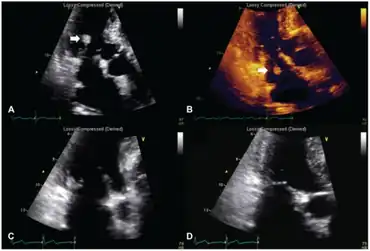

| a,b) Transthoracic echocardiography - NBTE arrow c.d) after anticoagulation therapy lesion practically disappeared | |